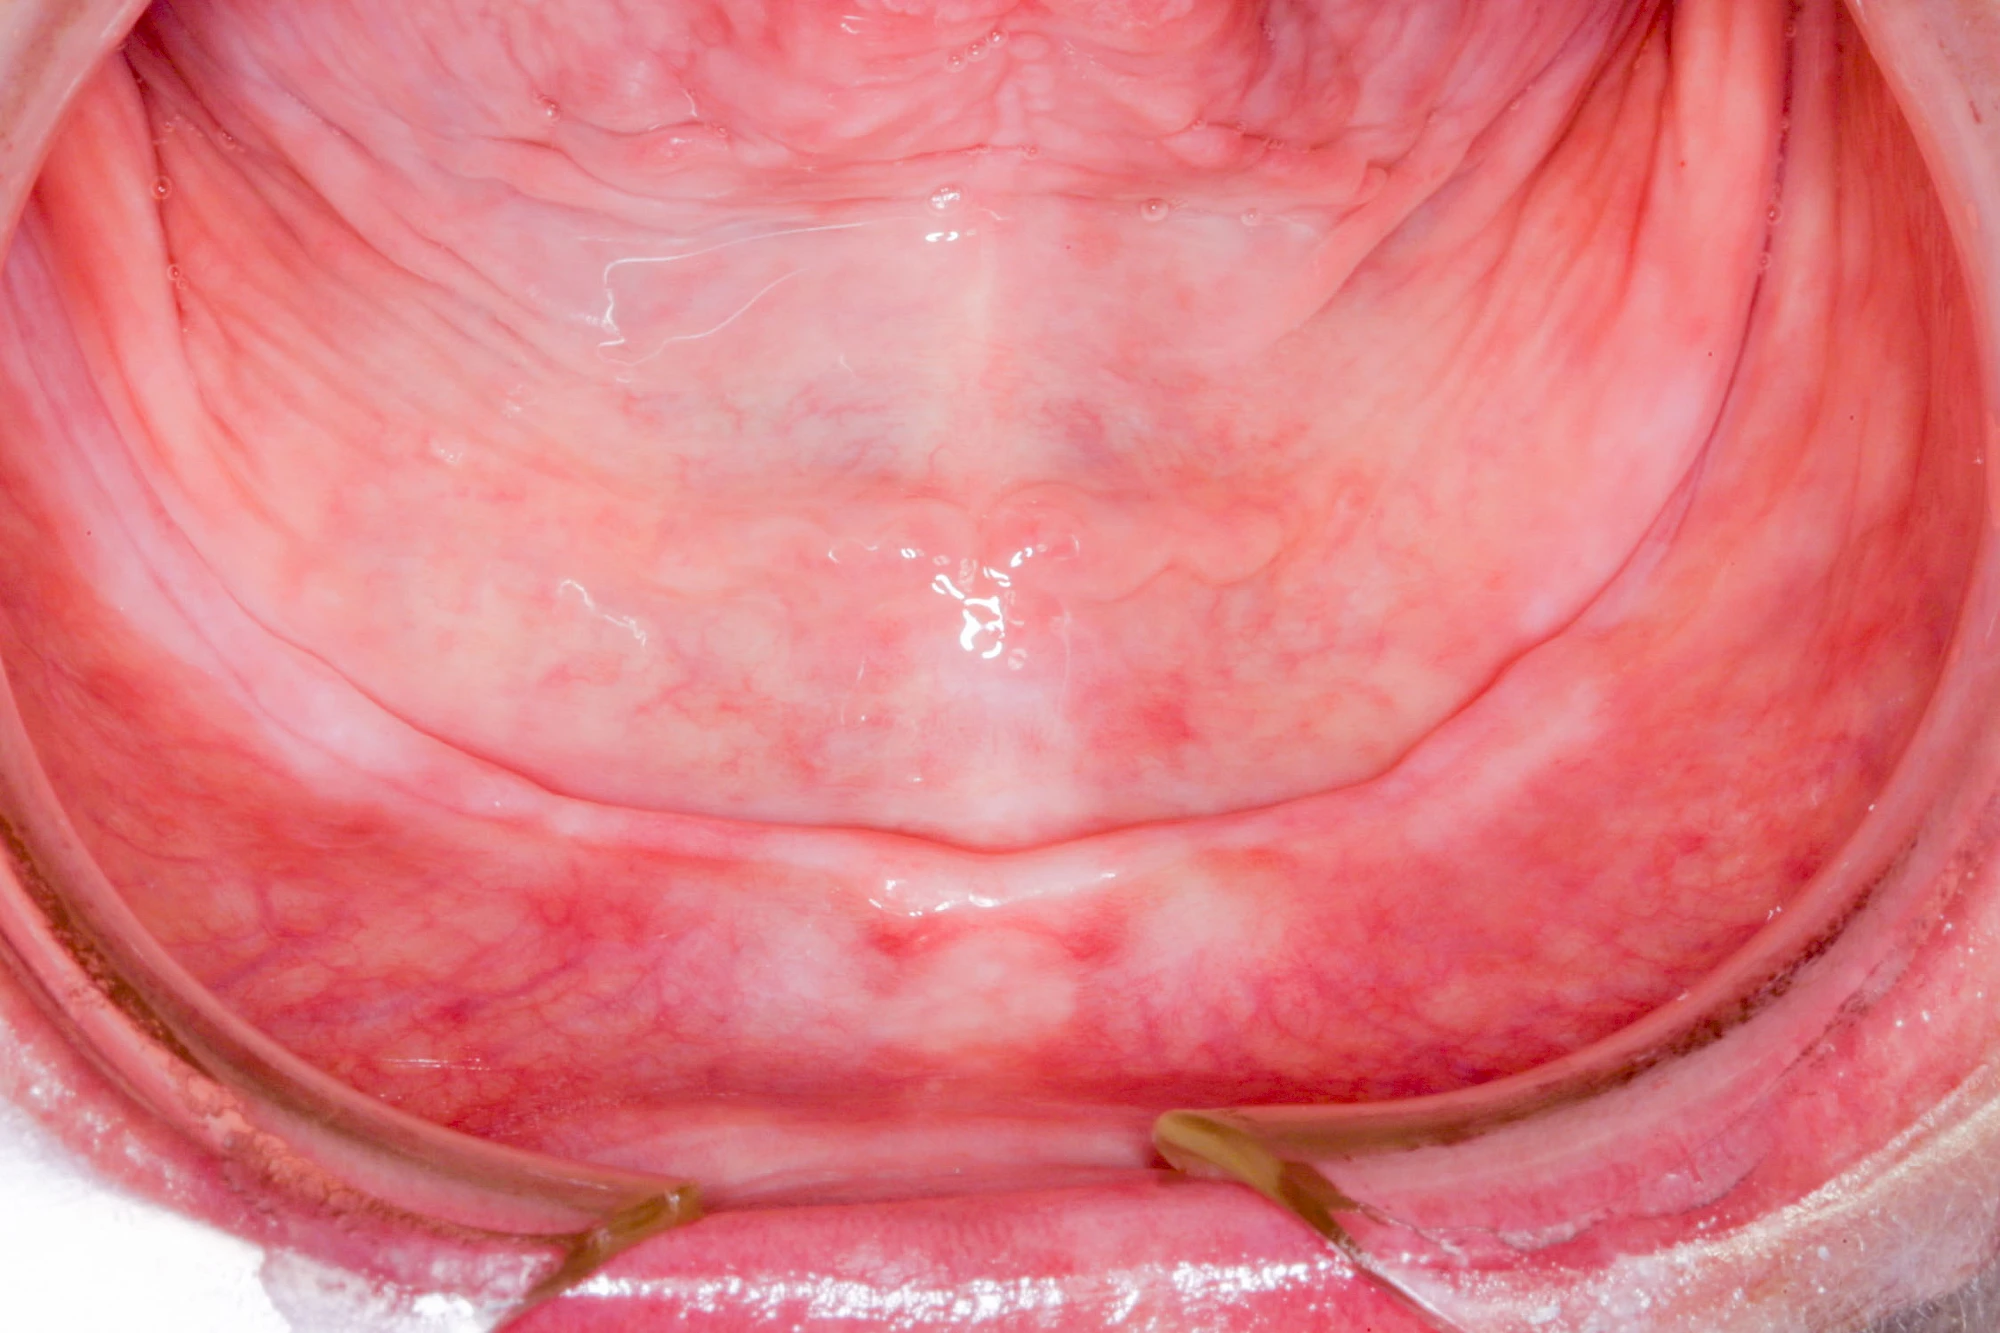

In seltenen Fällen schwindet nur der Knochen, aber nicht die bedeckenden Schleimhäute. In diesen Fällen spricht man von einem sogenannten "Schlotterkamm".

Auch wenn Zahnprothesen drücken, sollten vor allem Teilprothesen jeden Tag wenigstens für ein paar Minuten getragen werden, damit sich die eigenen Zähne nicht unbeabsichtigt verstellen und die Prothese weiter passt.